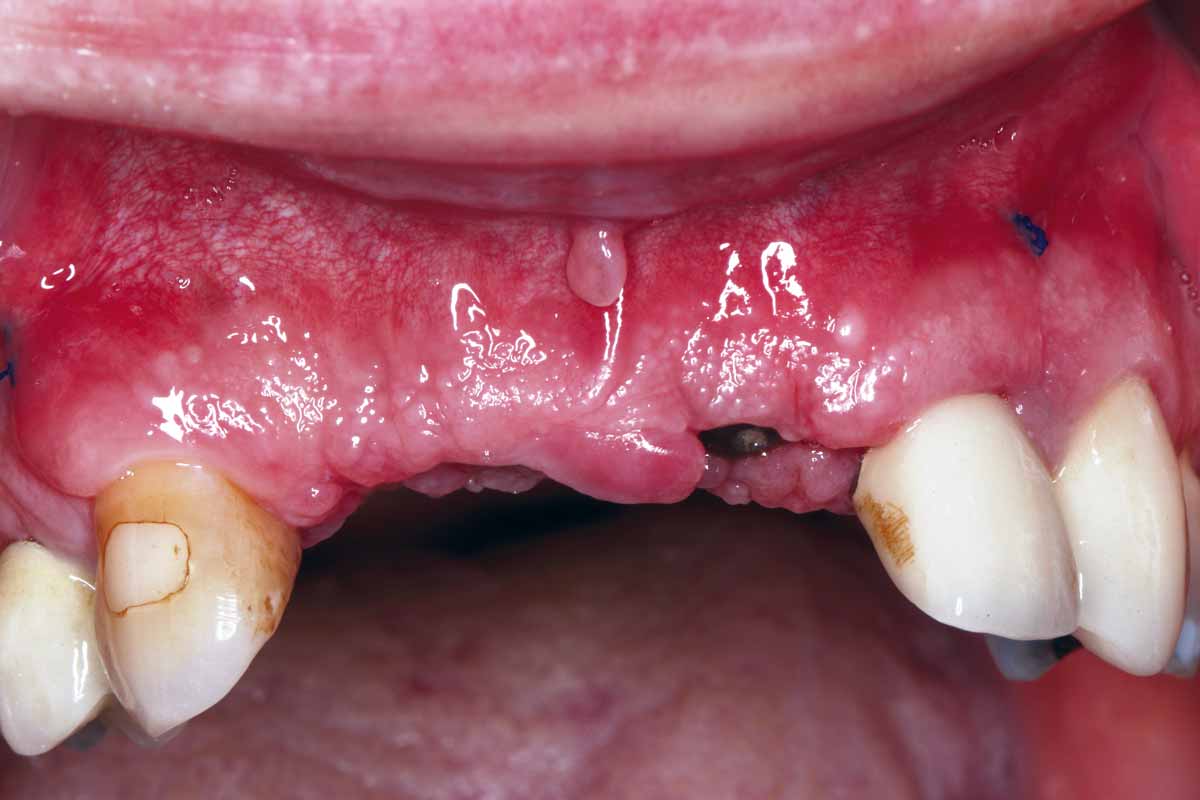

1/27 - Initial situation: missing teeth #11 & 12 and badly broken #21 root

GBR and soft tissue augmentation with cerabone® and mucoderm® - H. Maghaireh & V. Ivancheva